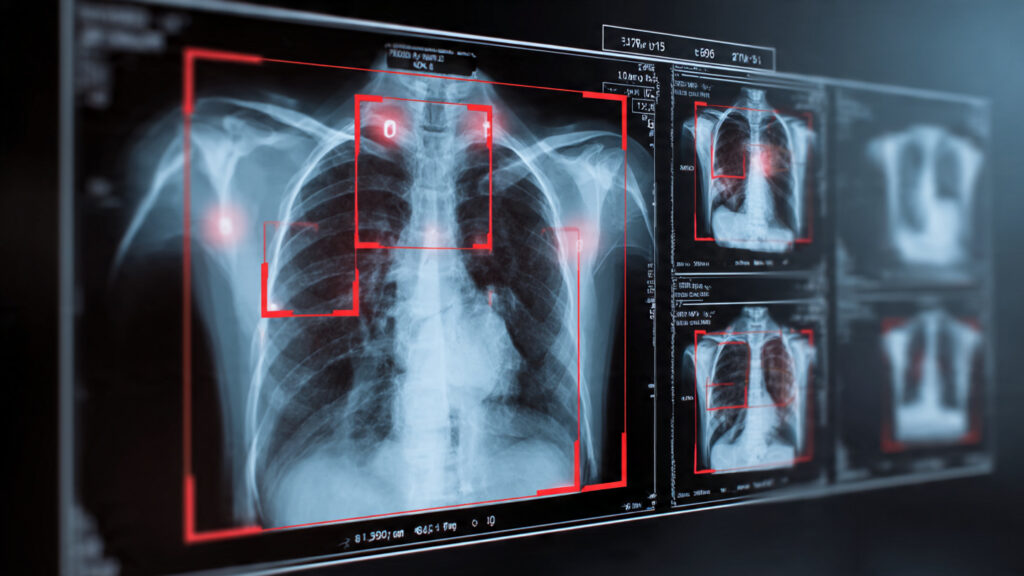

Medical Diagnosis

Object detection assists doctors by highlighting abnormalities in medical scans. Early detection of tumors can significantly improve patient outcomes.